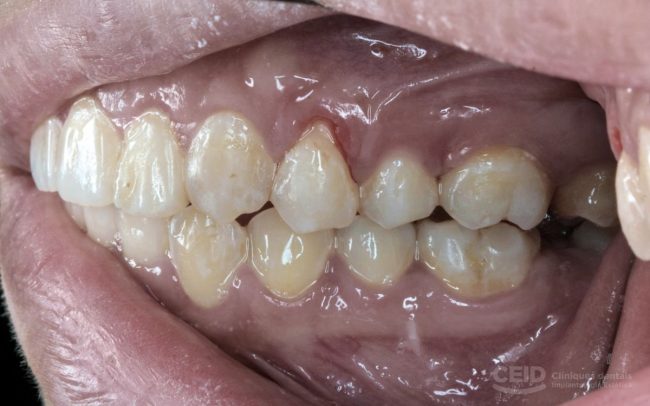

Empaste estético: Qué es, beneficios y cuándo se recomienda

En el mundo de la odontología moderna, cada vez más personas buscan tratamientos que no solo restauren la funcionalidad de sus dientes, sino que también mantengan o mejoren su estética dental. Uno de los procedimientos más populares para lograrlo es el empaste estético. En CEID Clínicas Dentales, ofrecemos soluciones personalizadas con materiales de última generación…